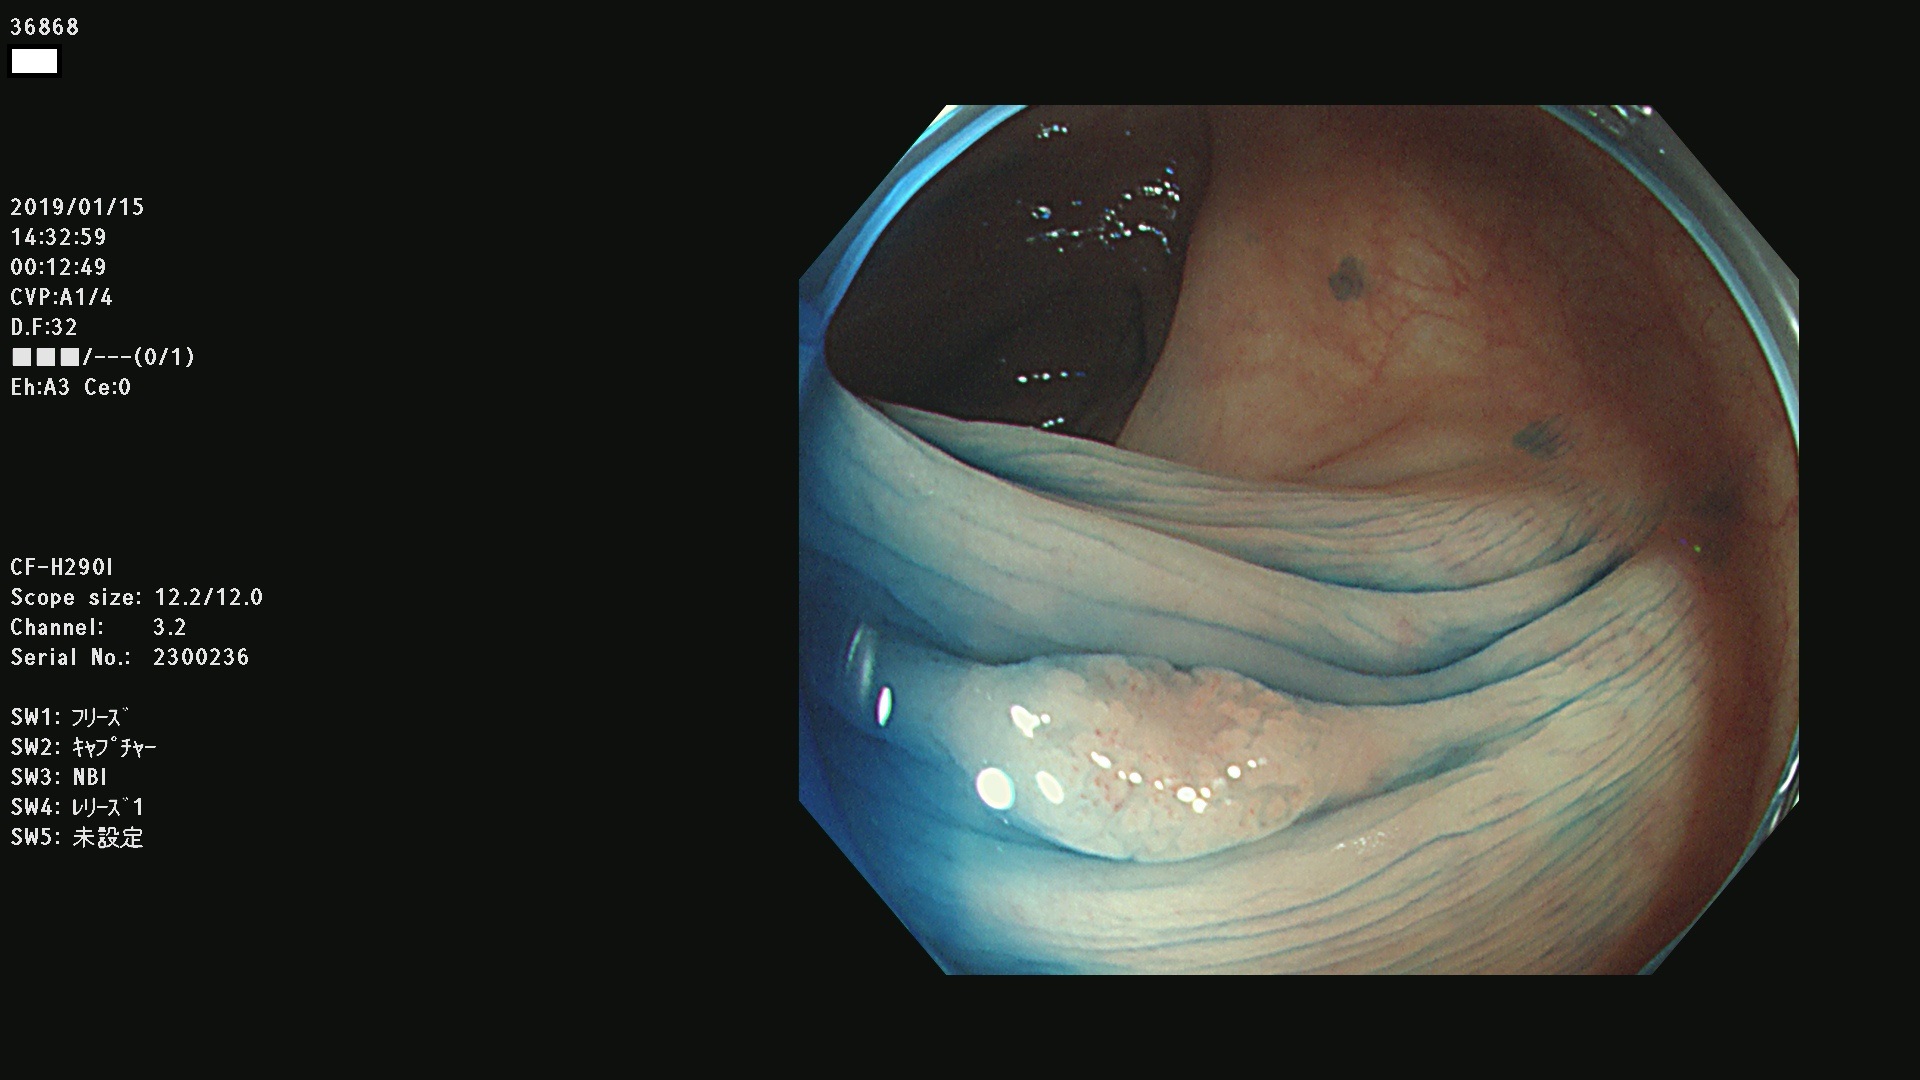

36804 36806 36807 36808 36809 36810 36811 36813 36815 36816 36817 36818 36820 36821 36822 36824 36825 36826 36828 36829 36830 36831 36832 36833 36834 36835 36837 36840 36841 36842 36845 36846 36848 36849 36851 36852 36853 36854 36855 36857 36859 36860 36861 36862(SSAPのみ) 36863 36864 36866 36868 36869 36870 36873 36875 36877 36878 36879 36881 36882 36883 36884 36885 36886 36887 36888 36889 36891 36892 36893 36894 36895 36896 36897 36898 36899

発見困難で危険性の高い平坦型病変(上記100名より抽出)